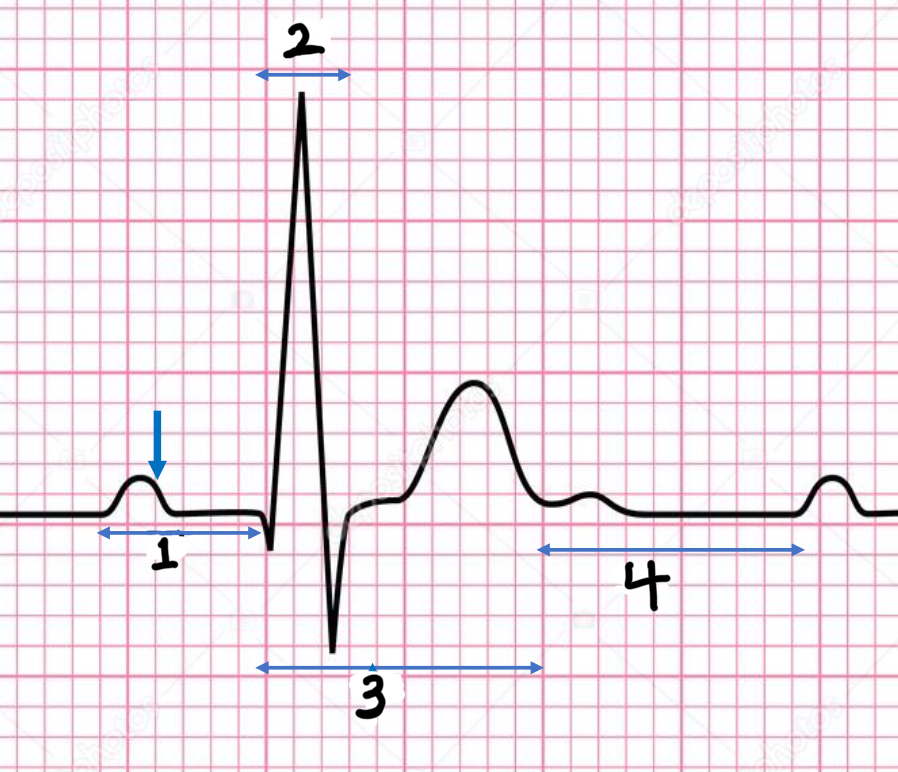

P wave

atrial depolarization

Precedes atrial contraction

QRS complex

ventricular depolarization

Precedes ventricular contraction

T wave

ventricular repolarization

PR interval

Name #1

QRS interval

Name #2

QT interval

Name #3

TP interval

Name #4

PR interval

time from beginning of the P wave to the beginning of the QRS complex

QRS interval

Time from beginning of the QRS complex to the end of the QRS complex

QT interval

Time from beginning of QRS complex to the end of the T wave

TP interval

Time from end of T wave to the beginning of P wave